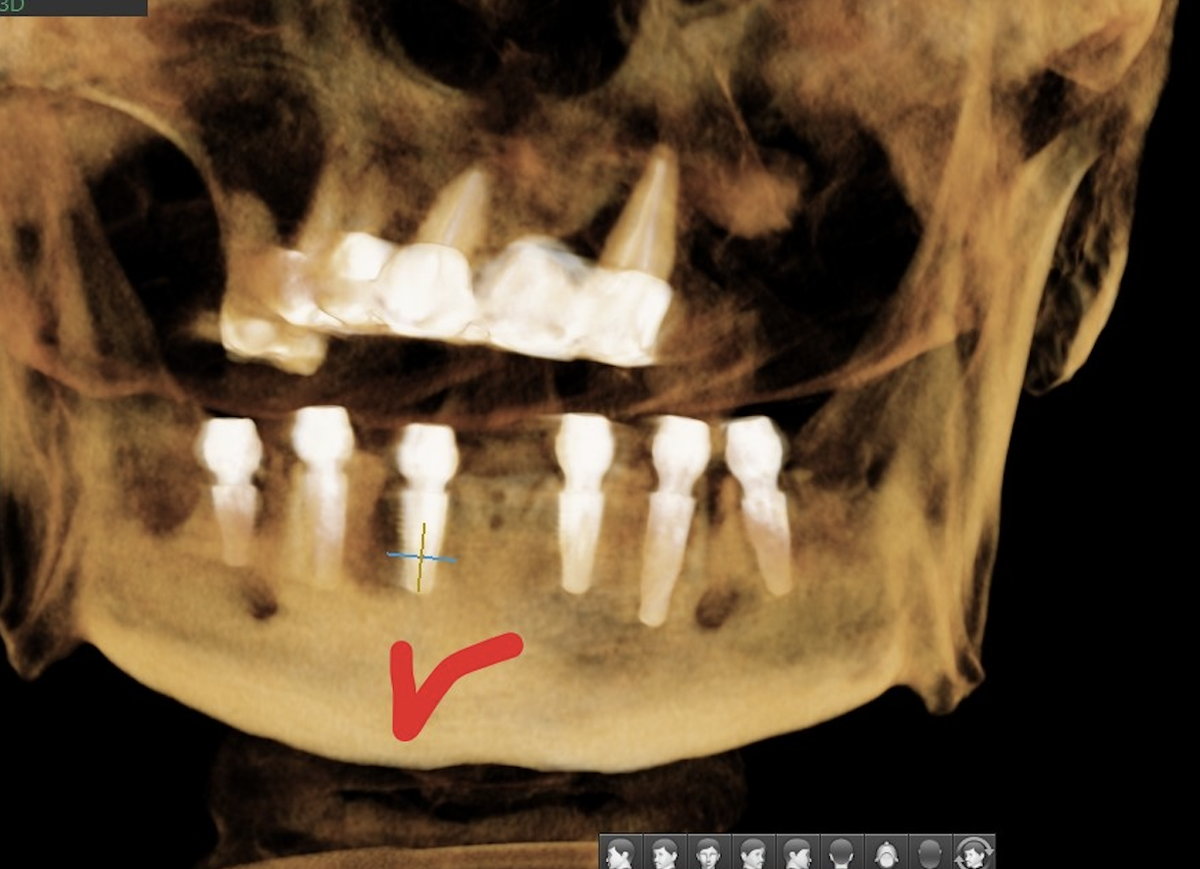

All-on-6 и All-on-8 - кому подходит

Шесть имплантатов - оптимальный баланс. Достаточно опор для надёжности, не избыточно для травматичности. Иногда, при особенностях кости, прикуса, повышенных эстетически требованиях могут быть установлены 8 имплантатов. Больше точно не нужно.

Преимущества 6 опор:

• нагрузка распределяется лучше - каждый имплантат несёт меньшую нагрузку;

• можно использовать имплантаты стандартной длины или короткие дистально;

• резерв прочности - потеря одного имплантата не критична, есть время на переустановку без потери комфорта;

• протезы длиннее.